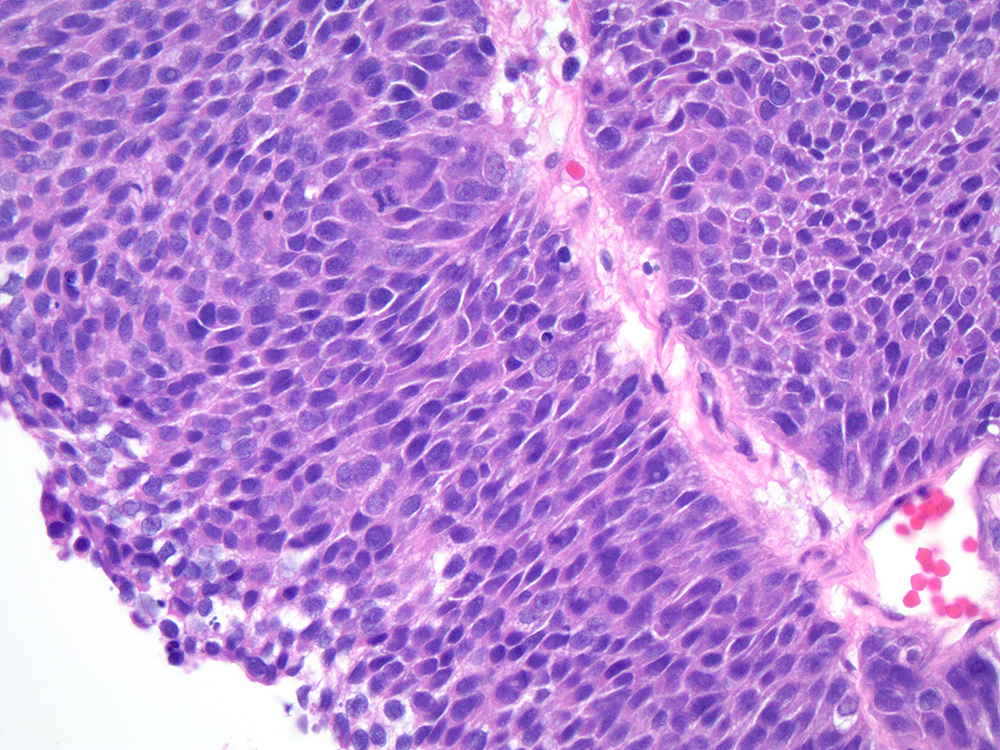

Bladder Papillary Lesions

Case ID: 458